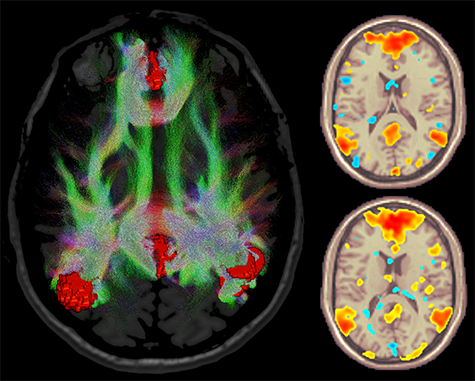

Jeder sollte Zugang zu Hochleistungs-MRT-Bildqualität erhalten. Aus diesem Grund haben wir für unseren SIGNA™ Premier eine 70 cm breite Patientenöffnung konstruiert. Wir haben eine Möglichkeit gefunden, die thermische Stabilität eines Hochleistungsgradienten in einer breiten Patientenöffnung zu erhalten. Die SuperG-Gradientenspulen-Technologie erhöht die Akquisitionsgeschwindigkeiten durch kraftausgeglichene Hohlleiter mit unabhängigen Kühlkreisläufen für die X-, Y- und Z-Achse. Durch direktes Kühlen jeder Gradientenschicht maximiert der SIGNA Premier den Arbeitszyklus für Human-Connectome-Protokolle (MultiShell DTI und hochauflösende fMRT) und hochauflösende Körper-, Skelett- und Herzbilder, ohne dabei Abstriche beim Patientenkomfort oder bei der Größe der Patientenöffnung hinnehmen zu müssen. Damit ist der SIGNA Premier das einzige MRT-System mit 60 cm Leistung in einer effektiv 70 cm breiten Patientenöffnung.

Größere Konsistenz und Stabilität für fortschrittliche fMRT

Eine hohle Gradientenspule mit kraftausgeglichener Konstruktion sorgt für hervorragende Stabilität bei anspruchsvollsten Anwendungen.